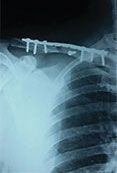

Case 6: Clavicle fracture

Displayed Clavicle fracture in a 24 years old cricketer

X-RAY 1

pre operative X-Ray showing displayed clavicle fracture

post operative x-ray showing fracture fixed with plate and screw